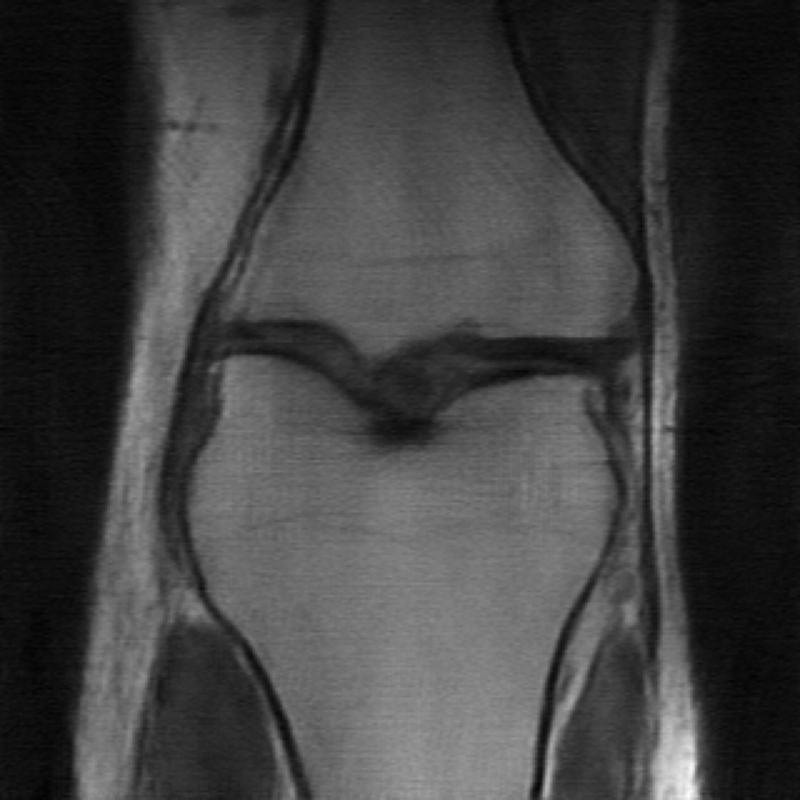

MRI reconstruction is performed with a undersampling of k-space in the phase encoding direction for both and . The sampling maps are shown in Fig 4.

| (a) Original k-space sampling pattern () | (b) Resampled k-space sampling pattern () |

The data used in the undersampled MRI experiments were obtained from the NYU fastMRI Initiative [45]. The primary goal of the fastMRI dataset is to test whether machine learning can aid in the reconstruction of medical images. We trained and tested on a subset of the single-coil knee dataset, which consist of simulated single-coil measurements. In all tests, we use complex-valued data, which interfaces with our deep networks by treating the real and imaginary parts of the images as separate channels. We measure reconstruction accuracy with respect to the center 320320 pixels of the complex IFFT of the fully-sampled k-space data. For the purpose of visualization, we display only the magnitude images in the following sections.

In the case of MRI, we use two choices of , depending on whether we assume is fully known or not. In the case is fully known, we utilize another undersampled k-space mask, but with resampled high-frequency lines. We display the original and new k-space sampling masks in Figure 4. To illustrate the utility of our approach under miscalibration of the forward model in an MRI reconstruction setting, we also consider a unknown random perturbation of the original k-space lines, which we attempt to learn during reconstruction. The vertical k-space lines are still fully sampled, as are the center 4 of frequencies, but all high frequency lines are perturbed uniformly at random with a continuous value from -2 to 2. We wish to emphasize that this experiment is not meant to reflect clinical practice, since such miscalibration of k-space sampling locations is not typically encountered in anatomical imaging with Cartesian k-space sampling trajectories. However, we include this experiment simply to illustrate that our approach could be extended to unknown parametric changes in the forward model in an MR reconstruction setting.